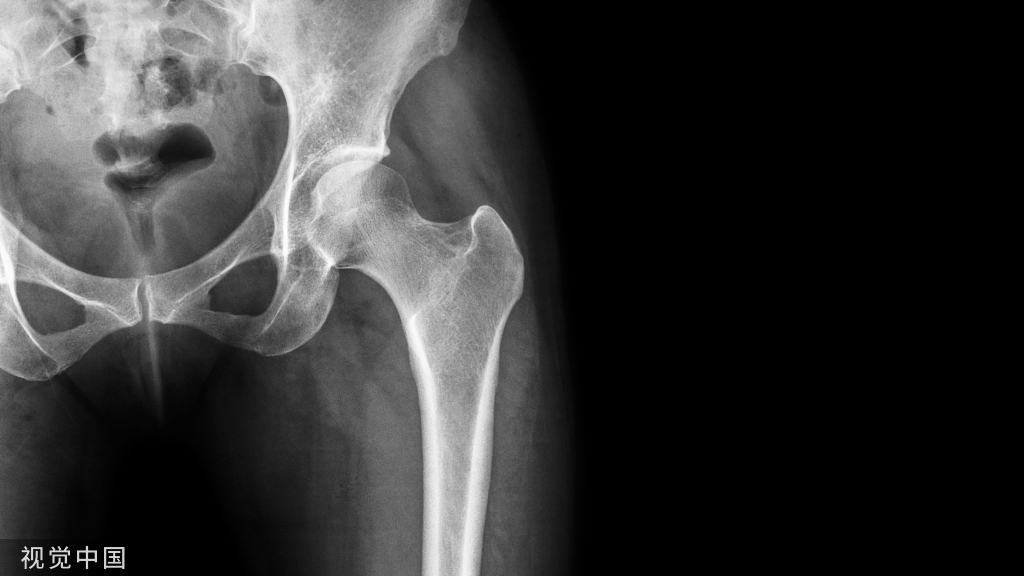

股骨远端单髁或双髁的冠状面骨折均称为Hoffa骨折。

Hoffa骨折属于比较少见的骨折类型,单纯Hoffa骨折占整个股骨骨折的0.65%;占全部股骨远端骨折的8.7%~13%。外髁Hoffa较内髁、双髁Hoffa多,占整个Hoffa骨折的78-85%。股骨髁上、髁间骨折合并Hoffa骨折者占38.1%。

股骨远端粗大并发生旋转,呈喇叭状,主要由松质骨组成,向两侧延伸即为股骨髁,为膝关节重要组成部分。

外侧髁较宽大,内侧髁较狭长,位置较低,内外侧髁间深凹为髁间窝,上有2个切迹,膝交叉韧带附着其上。前交叉韧带附着于外髁内面的最后部,后交叉韧带则附着于股骨内髁外面的前部。

因此,发生Hoffa骨折,骨折块上常附有股骨外侧髁或内侧髁后部突起的关节面。外侧髁骨折块常向后、外旋转移位,可有膝前交叉韧带和腘肌腱、腓肠肌外侧头附着;内侧髁骨折块常无后交叉韧带附着。